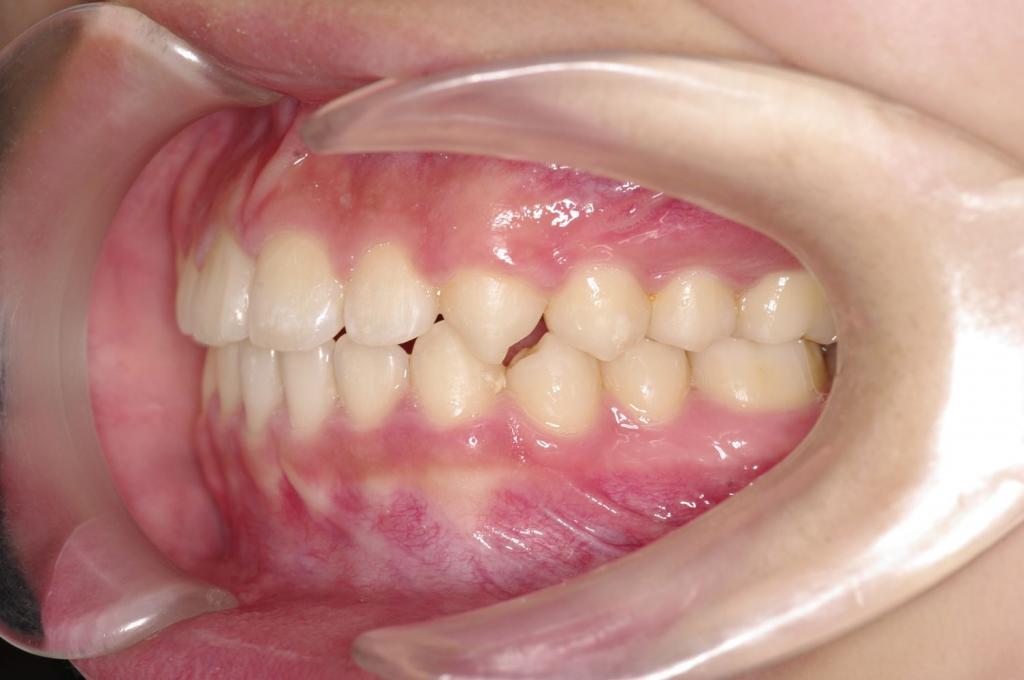

前歯、出っ歯・開咬の矯正治療

(治療期間、治療前後写真、治療方法、費用)WORKS